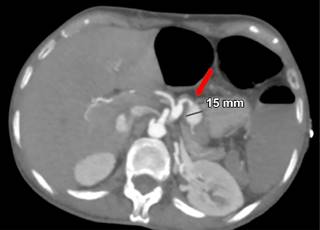

Mujer de 44 años quien 6 meses previos a su ingreso refiere disminución progresiva de la clase funcional debido a un soplo aórtico, por lo que se realizó cambio valvular con la necesidad de ser sometida a circulación extracorpórea y uso de vasopresores. Durante los primeros 10 días postquirúrgicos se diagnostica obstrucción intestinal, por lo que se realiza TC con hallazgo incidental de arteria esplénica (Figura 1) con dilatación aneurismática de hasta 12 mm, en un nuevo estudio de TC a las 24 horas (Figura 2) con ligero aumento del diámetro de aneurisma esplénico hasta 15 mm, pasadas 96 horas solicita nueva TC (Figura 3) y se evidencia mejor definición de la dilatación aneurismática de la arteria esplénica con diámetro actual de 15 mm (previamente de 12 mm). Con los hallazgos tomográficos previamente descritos, se pudo observar la evolución del proceso de dilatación aneurismática con ruptura contenida por el parénquima pancreático, la paciente cursó con un cuadro de obstrucción intestinal con desimpactación endoscópica y dolor abdominal, por lo que seguramente se enmascaró el cuadro clínico.

Figura 2: Tomografía computarizada a las 24 horas con ligero aumento del diámetro del aneurisma esplénico a 15 mm.